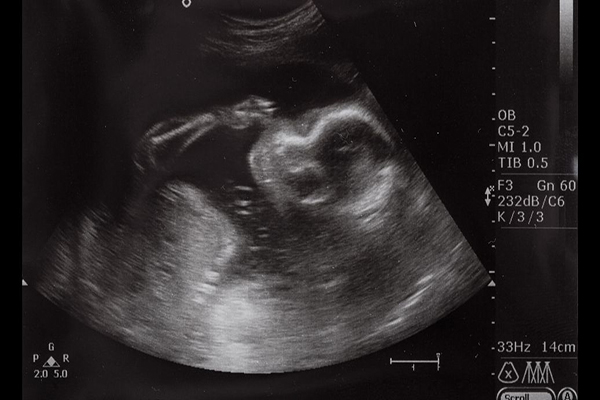

怀孕40天左右b超图片应该是怎么样子的?

怀孕40天左右尚未形成一完整的胚胎,此时b超图片一般可见圆形或椭圆形妊娠囊,部分还可见到胚芽和原始心管搏动。不过也不是每个人在这个时候都可以见到上述情况的,若是患者月经不规律,或者是受精卵着床比较晚,那么很有可能只能看到妊娠囊,而不能看到胎芽以及心管搏动。对于新手妈妈来说,基本上都很好奇怀孕40天左右,b超图片是怎么样子的。其实根据临床显示的数据来看,怀孕40天通过b超观察,可见圆形或椭圆形妊娠囊

怀孕40天b超图片上能看到胎芽吗?

能看到。不过具体能不能看到胎芽,还是要根据孕妇怀孕40天的真实情况来进行判断。如果孕妇的体质好、月经正常,那么胎芽的发育就会很快,此时是能清楚的在b超图上看到。但若是孕妇本身月经周期就不是很规律,再加上排卵晚亦或者是着床时间晚,那么此时就可能看不到。所以这是因人而异的,不能一概而论。胎芽的出现可以说明很多问题,一般来说,在相应的时期出现了胎芽,就预示一切顺利。也正因为如此,很多孕妇在孕40天去医院